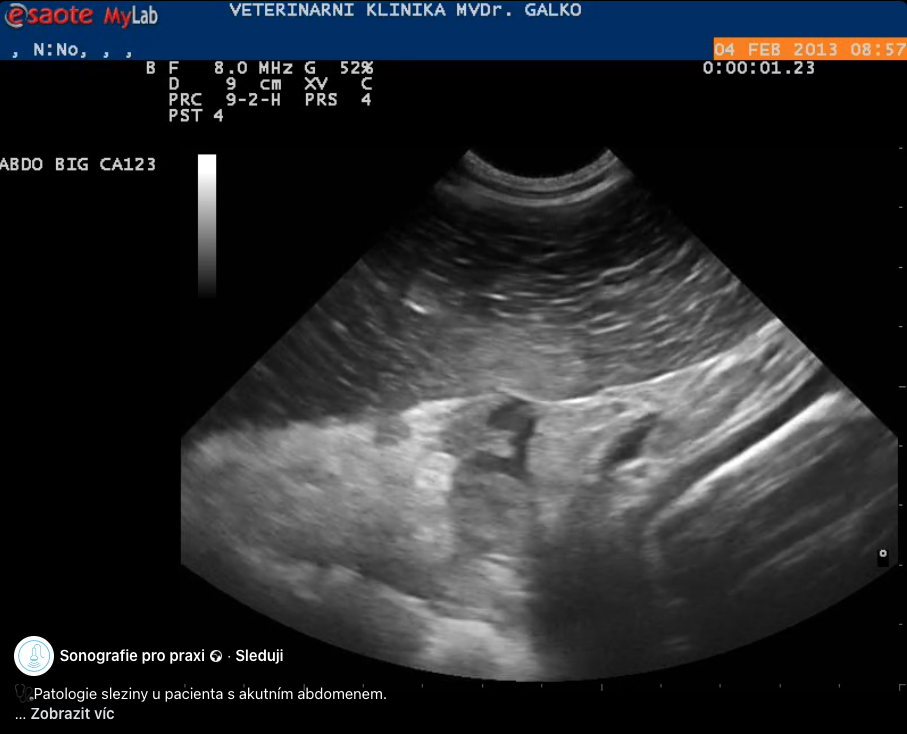

Tromboembolie sleziny

Akutní tromboembolická okluze a.lienalis s globální ischemickou reakcí parenchymu.